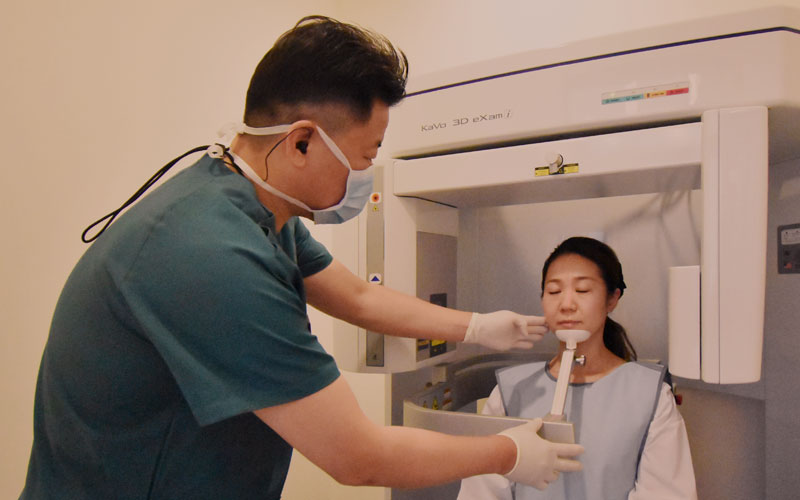

CT診断に精通している

インプラント治療を行う上で不可欠なのがCT診断です。当院では歯科用CTを導入して精密診断を行なっています。インプラントはわずか10mm程度の小さなものですが、埋め込み位置の内部には、目視できない骨の形状や神経・血管などがたくさんあり、無視して埋入することは不可能です。平面のレントゲン写真では把握ができないものも、CTであれば把握できるようになります。安心してインプラント治療を受けるには、CTが導入されていて、CT診断経験の豊富な歯科医院を選ぶ必要があります。